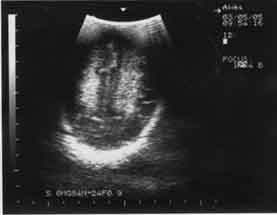

Кроме того, ишемический некроз проявляется повышением эхогенности обычно в острой фазе. В подострой и хронической фазах ведущую роль в диагностике играют неоднородность структуры, а также наличие участков с различной эхогенностью, в том числе кист. ПВЛ в подавляющем числе наблюдений является двусторонним процессом (рис. 1,2).

Рис. 1 Новорожденная Б 11 суток, СГ – 29 недель, ПВЛ III-IV степени на фоне повышенной эхогенности – мелкие анэхогенные образования (формирование кист). | Рис. 2. 10 суток, СГ – 30 недель, ПВЛ III степени, гиперэхогенность в перивентрикулярном пространстве (до образования кист). |

Эхографическое выявление острой фазы ПВЛ в первые сутки жизни может быть затруднительным. Это обстоятельство диктует необходимость динамического эхографического наблюдения за недоношенными детьми независимо от наличия или отсутствия у них морфологической картины поражения ЦНС в первые трое или даже семь суток жизни. С момента начала некротического процесса в веществе мозга до образования кисты обычно проходит 10-14 дней (рис.1,2). Во всех случаях перивентрикулярный некроз со временем приводит к пассивной внутренней гидроцефалии, которая может развиться через 2-3 недели после рождения.